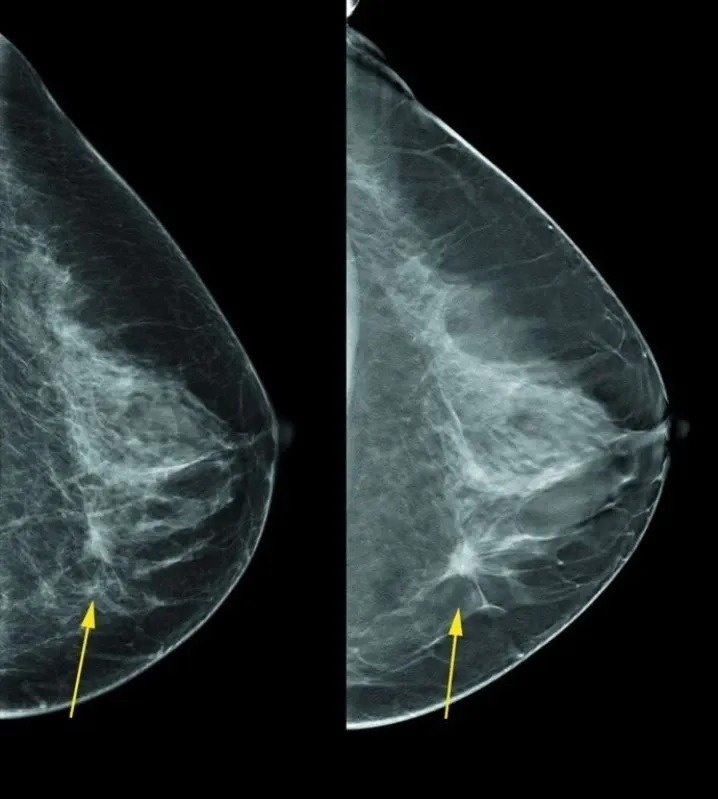

Em casos suspeitos ou para complementar a avaliação, podem ser solicitados exames complementares, como a mamografia, ultrassonografia ou ressonância magnética das mamas.